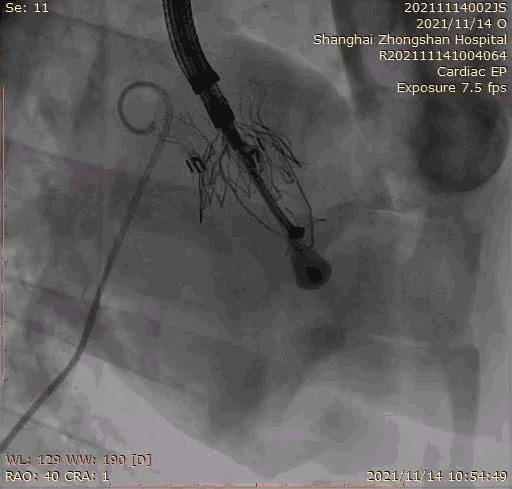

2021年11月14日星期日,復(fù)旦大學(xué)附屬中山醫(yī)院(以下簡(jiǎn)稱中山醫(yī)院)葛均波院士團(tuán)隊(duì)成功應(yīng)用經(jīng)血管介入三尖瓣置換產(chǎn)品Lux-Valve Plus完成臨床前研究,并獲得圓滿成功!此次研究的成功預(yù)示經(jīng)血管三尖瓣產(chǎn)品Lux-Valve Plus已完成臨床前準(zhǔn)備,即將開啟后期的正式臨床研究!

本次臨床前研究經(jīng)右側(cè)頸靜脈置入LuX-Valve Plus輸送系統(tǒng)可調(diào)彎鞘管,在DSA及超聲引導(dǎo)下將人工三尖瓣瓣膜植入到原有三尖瓣位置,利用獨(dú)特的錨定技術(shù)將人工瓣膜支架可靠固定在預(yù)定的位置。